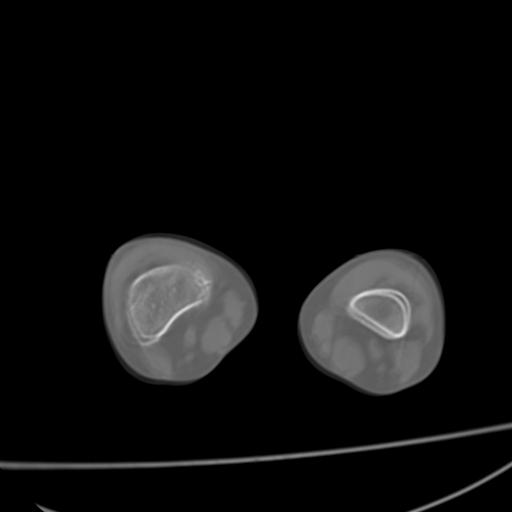

标题: PED0940:M12Y,左股骨下端酸痛畸形 [打印本页]

标题: PED0940:M12Y,左股骨下端酸痛畸形

12岁男孩,左膝关节肿痛8年,近月明显

内生骨软骨瘤?

血友性关节病?